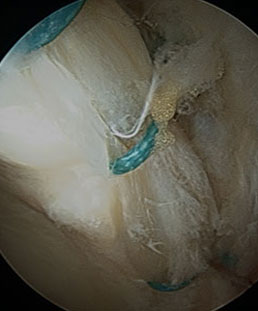

How do I know whether my surgeon can treat my Hip Labral Tear and FAI? – Derek Ochiai, MD

Many times, the diagnosis of a hip labral tear is [...]